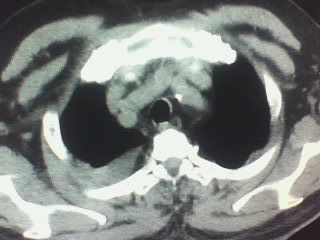

以下是引用随光逐影在2009-9-26 22:31:00的发言:[br]支持 右肺中叶炎症,双侧胸腔积液伴右肺下叶膨胀不全;急性胆囊炎,右肾囊肿,腹水,右侧肾周筋膜增厚。

以下是引用zjzjr在2009-9-26 22:28:00的发言:[br]右肺中叶炎症,急性胆囊炎,双侧胸腔积液伴右肺下叶膨胀不全,腹水,右肾囊肿.右侧肾周筋膜增厚.